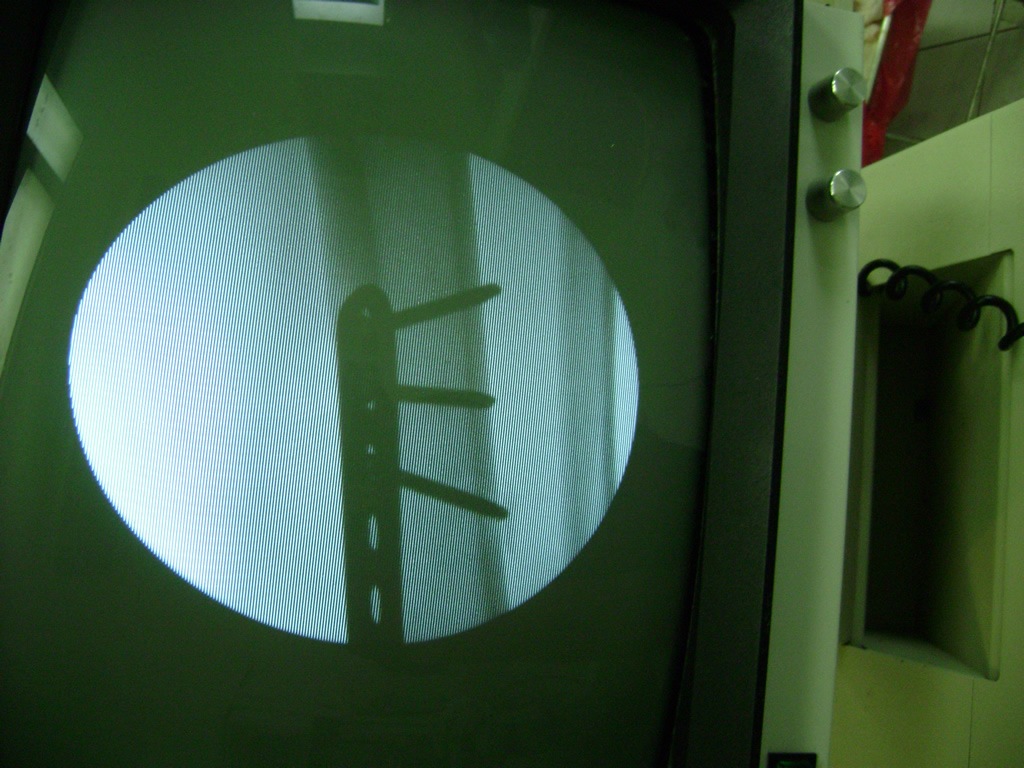

Cirugías de Codo - Perone y Tibia

Aunque cada uno de estos huesos puede fracturarse por separado, normalmente la rotura es una lesión que se produce de forma conjunta

La mayor parte de las roturas implican a la parte proximal del hueso (parte del hueso próximo a la rodilla) o a la parte distal (parte del hueso cerca del tobillo).

Debido a la fina cobertura de piel que recubre la tibia y el peroné, las fracturas generalmente son abiertas, es decir, el hueso roto rasga la piel, atravesándola. Las fracturas de tibia y peroné generalmente se producen por un fuerte impacto o torsión.